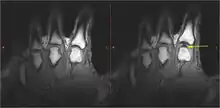

There were several hypotheses to explain the cracking of joints. Synovial fluid cavitation has some evidence to support it.[10] When a spinal manipulation is performed, the applied force separates the articular surfaces of a fully encapsulated synovial joint, which in turn creates a reduction in pressure within the joint cavity. In this low-pressure environment, some of the gases that are dissolved in the synovial fluid (which are naturally found in all bodily fluids) leave the solution, making a bubble, or cavity (tribonucleation), which rapidly collapses upon itself, resulting in a "clicking" sound.[11] The contents of the resultant gas bubble are thought to be mainly carbon dioxide, oxygen and nitrogen.[12] The effects of this process will remain for a period of time known as the "refractory period", during which the joint cannot be "re-cracked", which lasts about 20 minutes, while the gases are slowly reabsorbed into the synovial fluid. There is some evidence that ligament laxity may be associated with an increased tendency to cavitate.[13]

In 2015, research showed that bubbles remained in the fluid after cracking, suggesting that the cracking sound was produced when the bubble within the joint was formed, not when it collapsed.[9] In 2018, a team in France created a mathematical simulation of what happens in a joint just before it cracks. The team concluded that the sound is caused by bubbles' collapse, and bubbles observed in the fluid are the result of a partial collapse. Due to the theoretical basis and lack of physical experimentation, the scientific community is still not fully convinced of this conclusion.[3][14][15]